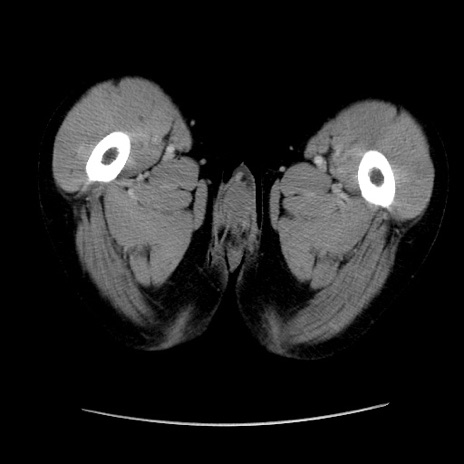

症例37(横断像)

【症例】40歳代 男性

【主訴】腹痛

【現病歴】4時間ほど前に電車に乗車中に臍部上より腹痛出現。徐々に増悪し起立困難となり、救急外来受診。生ものは数日食べていない。今朝お雑煮を食べた。

【身体所見】BT 36.8℃、BP 117/84mmHg、HR 91/min、SpO2 97%、苦悶様、腹部:臍上部広範囲圧痛あり、反跳痛±

【データ】WBC 8100、CRP 0.03